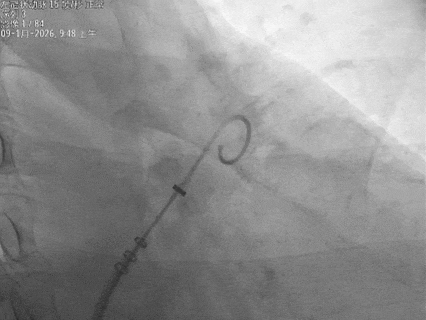

保持输送系统张力,退鞘使封堵器展开,封堵器锚定位置良好

封堵器骨架和鞘管、心耳长轴的同轴性良好,持续退鞘,封堵器充分展开

封堵器展开后造影

封堵器展开后肝位造影,封堵器完全封堵,无残余分流

牵拉试验

回弹明显,封堵器稳定锚定在心耳内部

释放后评估,封堵器位置稳定且未见残余漏

封堵器在心耳内展开后造影,显示无残余分流,

且在超声下封堵器完全堵住心耳